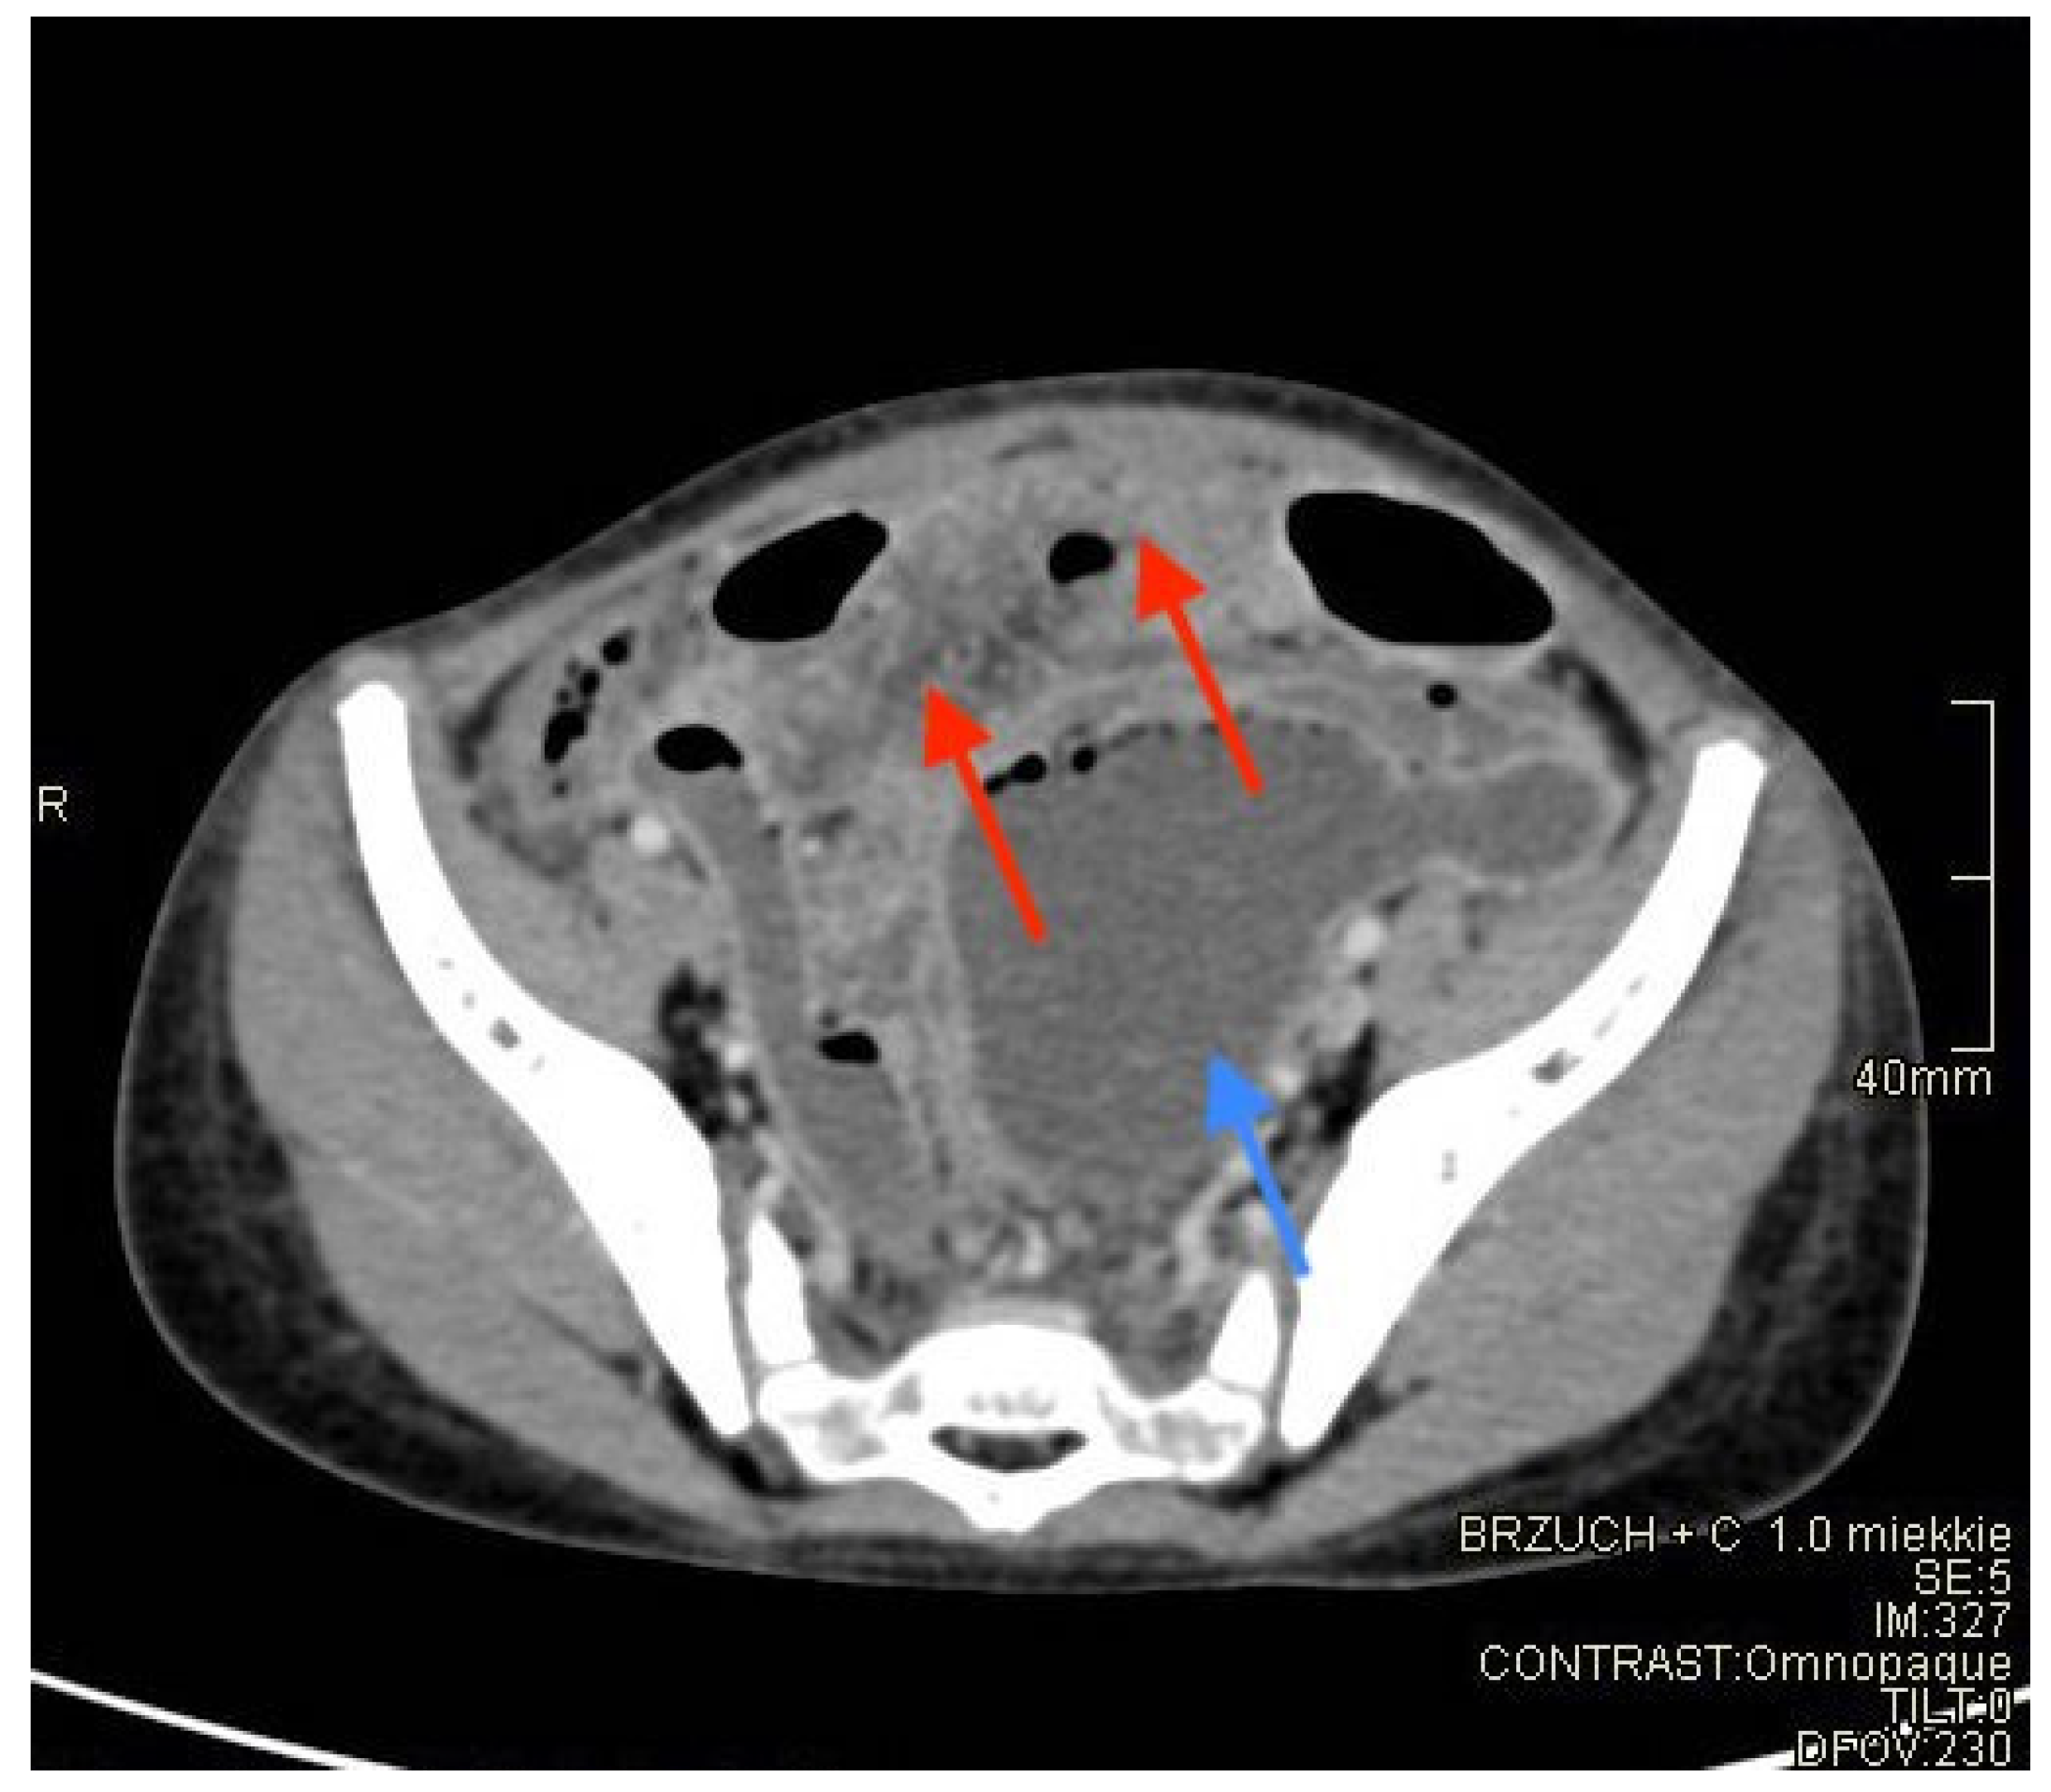

2. Case Presentation